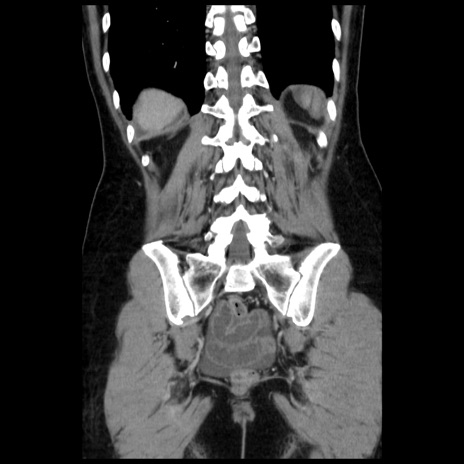

横断像

矢状断像